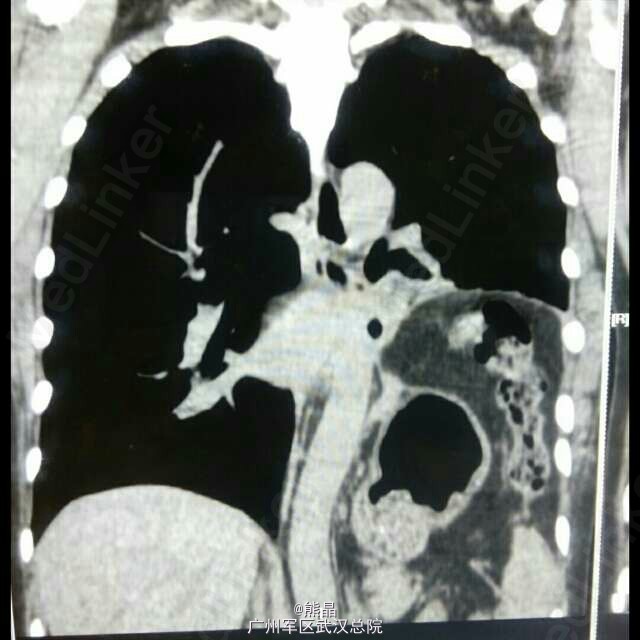

食管憩室术后

食管憩室

此病例为县医院食管憩室手术后病人,来本院做钡餐,钡餐是我做的,高度怀疑膈疝,后做了CT三维确诊。 大家可以看看图,哪里有不明白的可以问我。